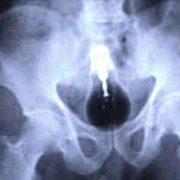

Батерии